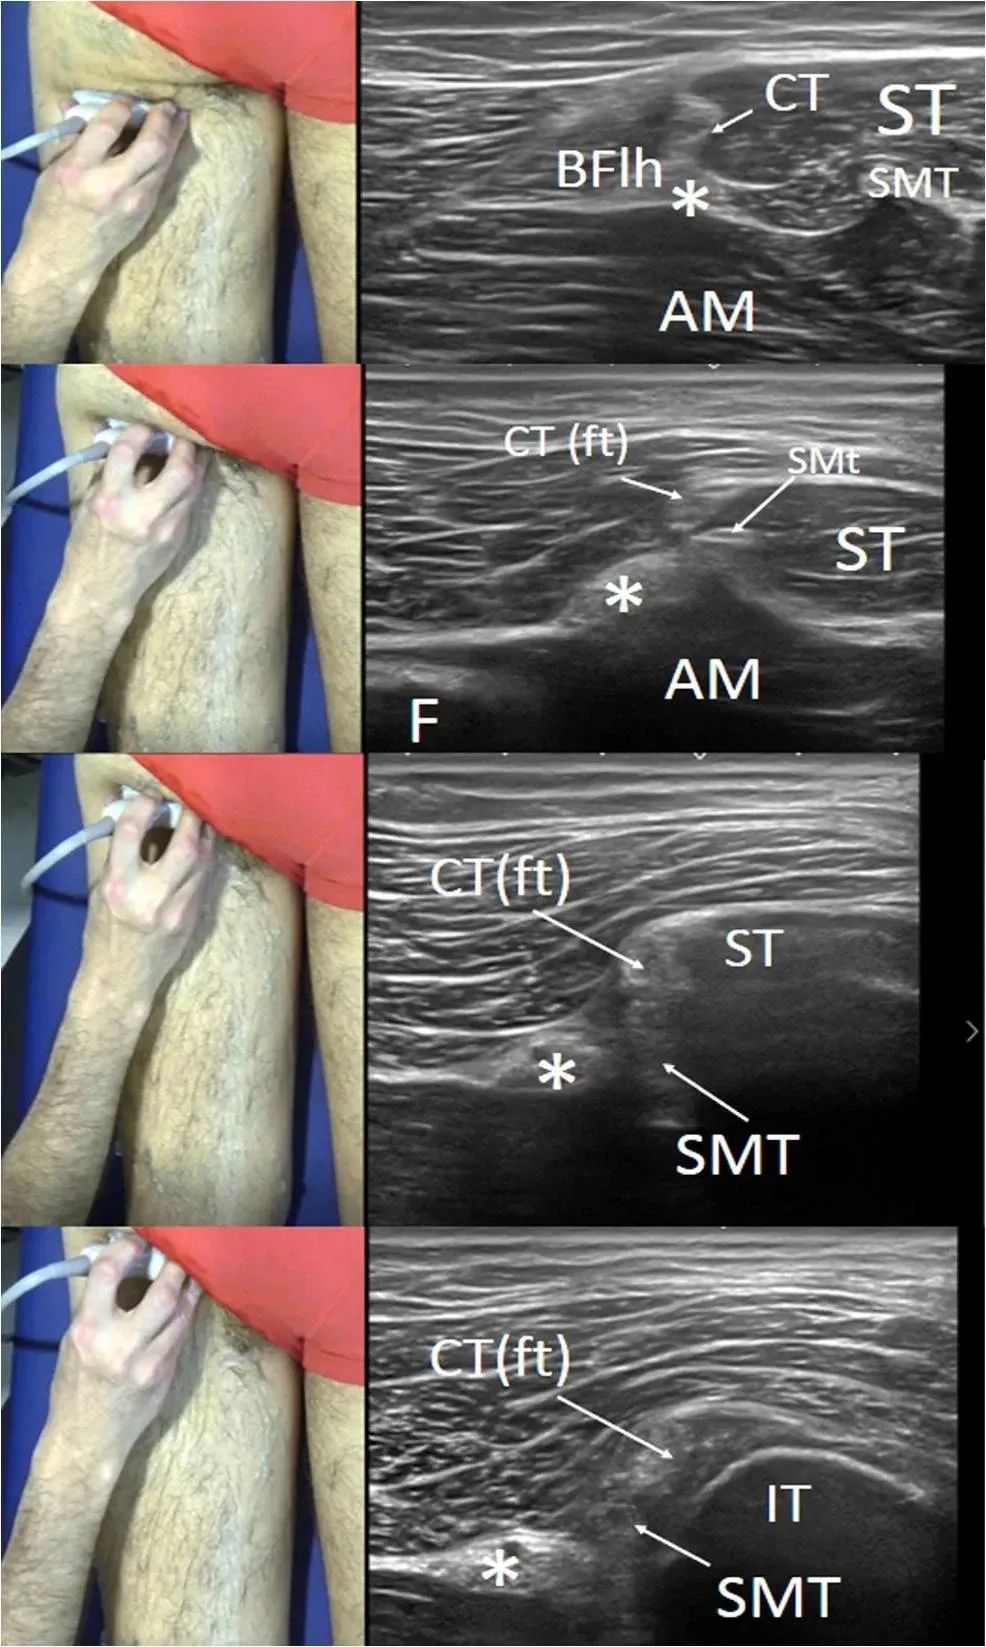

(圖4:短軸超聲掃描顯示腘繩肌近端部分(音叉手柄)的不同視圖。當探頭向近端方向移動時,可以看到總腱和半膜肌腱的部分接近坐骨神經(jīng),直到觀察到高回聲線,并具有與坐骨結(jié)節(jié)一致的后聲影。BFlh股二頭肌長頭、ST半腱肌、AM大收肌、SMT半膜肌腱、CT總腱、*CT (ft)*總腱游離腱部分、( *** ) 坐骨神經(jīng)。圖左側(cè)的照片表示探頭定位。)

相比 MRI,超聲還可用于評估坐骨結(jié)節(jié)中腘繩肌的起源及其與坐骨神經(jīng)的關(guān)系。在坐骨結(jié)節(jié)中,腘繩肌的起點靠近坐骨神經(jīng),坐骨神經(jīng)位于更外側(cè)。為此,我們需要一個表面標志,例如,就在股溝的尾部。可以看到那里的半腱肌 (ST) 肌纖維,因為這塊肌肉直接到達坐骨結(jié)節(jié)。當探頭向遠端移動時,可以看到股二頭肌 (BF) 的肌肉部分像三角形一樣變寬,而半腱肌 (ST) 的尺寸也增加。

在股二頭肌 (BF)/半腱肌 (ST) 共同肌腱的起源,可以看到坐骨結(jié)節(jié)的外側(cè),有更多的高回聲和淺表外觀。也可以看到半膜肌 (SM)肌腱(也有回聲),它在更外側(cè)、更深、更靠近坐骨神經(jīng)部分。

通過改變探頭超聲波束的角度,可以產(chǎn)生一定程度的各向異性,這有助于區(qū)分半膜肌 (SM)和聯(lián)合腱。這對于區(qū)分損傷是位于聯(lián)合肌腱還是半膜肌 (SM)肌腱,以及超聲引導或手術(shù)治療非常重要。共同肌腱和半膜肌 (SM)的截面與音叉手柄在短軸上重合。